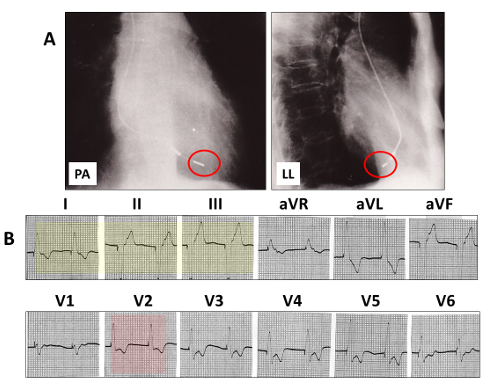

The QRS axis is markedly left with aright bundle branch block.

This is left ventricular pacing from an area very low, near the apex of the heart.

It is identical to a lead in the middle cardiac vein:

A: The cardiac silhouette with a lead tip (red open rings), close to the apex in the postero-anterior (PA) view and passing posterior in the left lateral (LL).

B: the pacing QRS is left axis deviation (yellow highlight) and right bundle branch block (red highlight).